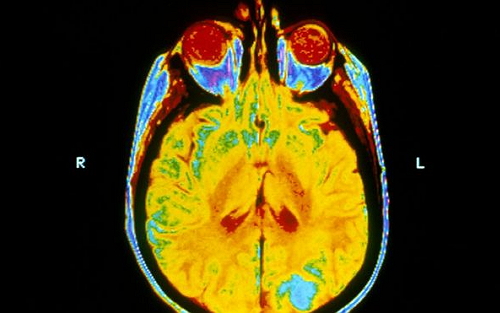

盡管并沒有隨機臨床試驗顯示全腦放療能改善患者的生活質(zhì)量或生存率,但是全腦放療(Whole brain radiotherapy,簡稱WBRT)仍廣泛用于肺癌腦轉(zhuǎn)移患者的治療。

據(jù)悉,在英國每年有超過45000人被診斷為肺癌。一般情況下,1/3的肺癌細(xì)胞會擴散到腦部。在過去,肺癌患者的繼發(fā)性腦腫瘤(或轉(zhuǎn)移)通常采用全腦放射治療。但這種方式會導(dǎo)致嚴(yán)重的副作用,包括惡心和極度疲勞,并對神經(jīng)系統(tǒng)造成損害。

這項研究,涉及來自英國的醫(yī)院的醫(yī)生、研究人員和患者,發(fā)現(xiàn)經(jīng)過一個星期的全腦放射治療后,患者的生活質(zhì)量沒有改善,且這些患者往往已經(jīng)有一個不良的預(yù)后。